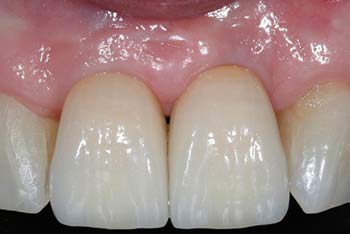

4 month post-op

final prosthesis

MinerOss Cancellous case images courtesy of Bach Le, DDS, MD, FICD, FACD